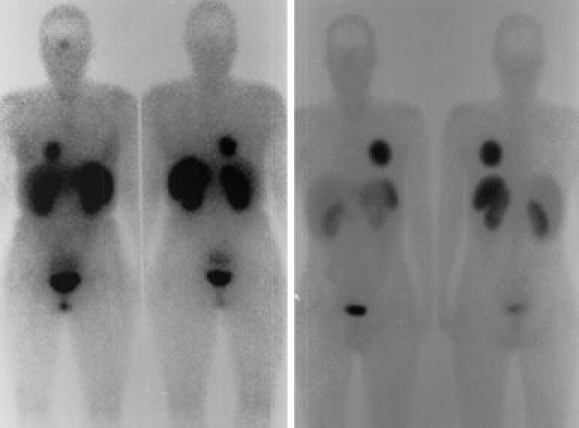

Fig. 6.

Octreoscans of the patients 2 and 3. In the female patient (left panel) the tumor is seen in the right lower lobe of the lung and also the positive staining of the pituitary gland. The male patient (right panel) had a large tumor in the left lung, without pituitary staining

Case 3. A 27-year-old male was referred in 1997 to our center. He had a 9-year history of hyperhydrosis, acral enlargement and headaches. Examination revealed moderately advanced features of acromegaly. The circulating GH concentration was elevated at 110 mU/l and decreased insufficiently to 52 mU/l following glucose administration, and IGF-I was elevated to 63 nmol/l (normal upper level at this age 32 nmol/l). Thyroid and adrenal functions were normal, but prolactin concentration was elevated to 21 μg/l (normal upper limit for males 6 μg/l). Other investigations performed (TRH test and the i.v. octreotide test) are summarized in Fig. 3. TRH bolus injection (200 μg i.v.) caused a ∼8-fold increase of GH and a 2-fold increase of PRL. Octreotide (50 μg i.v) caused a 94% inhibition of GH (Fig. 3). MRI scanning of the pituitary gland showed a macroadenoma II AE (Hardy classification, modified by Wilson [12, 13] see Fig. 4). He was treated for 6 months with sc octreotide (100 μg tid). The size of the adenoma decreased slightly, but because of the moderate clinical response to medical treatment and failure of normalization of GH and IGF-I, pituitary surgery was advised. One day before surgery a chest X-ray was taken, showing a large parahilar lesion (Fig. 5). CT scanning of this lesion was classified by the consultant pulmonologist and radiologist as a bronchial cyst and apparently unrelated to acromegaly. During pituitary surgery the adenoma was removed completely, but the neurosurgeon remarked that the consistency of the adenoma was firmer than normal. Since we suspected that the lung tumor was potentially a GHRH-producing source, postoperative investigations were focused on this possibility. After surgery, MRI scanning of the pituitary region did not show residual tumor, GH concentrations decreased considerably and PRL concentrations became normal. GH dynamic tests did not completely normalize: GH increased after TRH injection from 4.63 mU/l to 22.1 mU/l and after glucose loading GH decreased from 4.33 mU/l to 2.56 mU/l (normal value below 1 mU/l). During an i.v. octreotide test GH decreased from 6.21 mU/l to 0.85 mU/l, but treatment with this drug was not reinstituted. On 111In-labelled-octreotide scanning the tumor was positive (see Fig. 6).